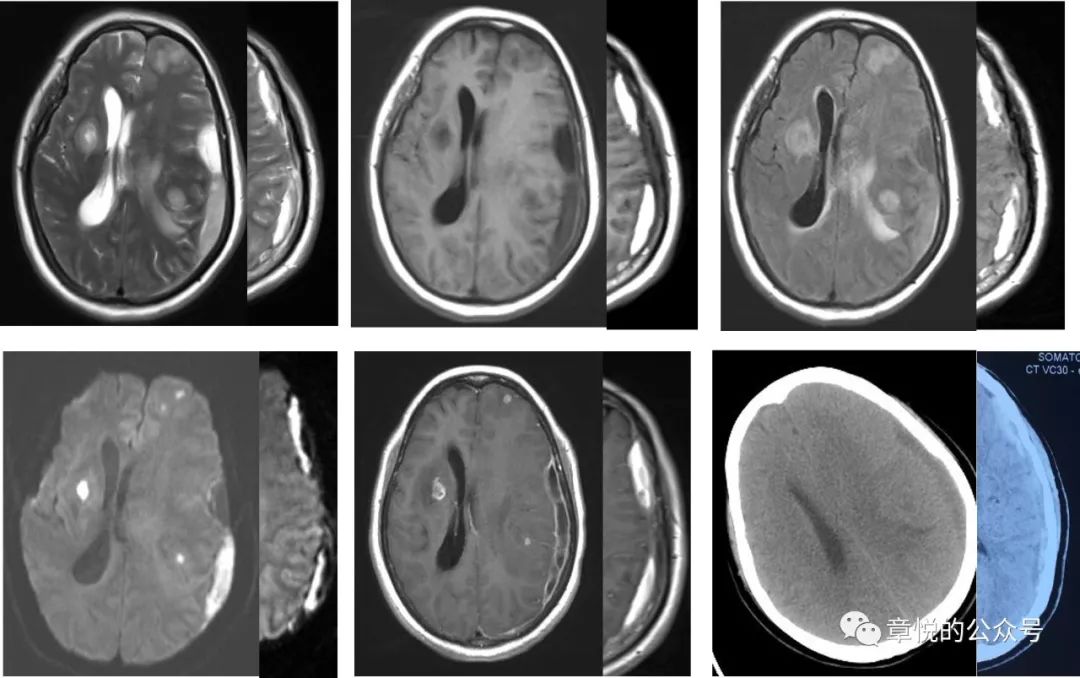

5. 癫痫后的脑功能损害

病人入院后癫痫频发,那会不会是癫痫后的表现呢?癫痫持续状态后出现磁共振异常表现的概率为11.6%,主要的改变有海马受累,胼胝体压部受累,皮层加丘脑受累,皮层受累和小脑交叉性失联络等(图8),影像改变能持续多长时间没有大宗报道,从小样本的研究看,部分病例在发病2周时仍旧有信号改变,这一点我们的案例倒是符合的。

图8 癫痫后脑磁共振异常的形态,海马受累,胼胝体压部受累,皮层加丘脑受累,皮层受累和小脑交叉性失联络等。(Milligan TA. et alFrequency and patterns of MRI abnormalities due to status epilepticus. Seizure- European Journal of Epilepsy , Volume 18 , Issue 2 , 104 – 108)

患者入院后,我们发现他的血糖十分高,空腹血糖11 mmol/L,餐后高达18 mmol/L,糖化血红蛋白超过11%,起初家属对我们提出的胰岛素治疗有点感冒,但连续3天患者情况不好于是就听从我们的意见,晚上一针下去,第二天早上血糖降到7 mmol/L,患者意识障碍明显好转,并且能够连词成句了,家属对此十万分的满意,毕竟是华山医院,一针见效!此后的几天,病人空腹血糖基本就控制6-7 mmol/L,餐后血糖8-9 mmol/L,病人情况一天好过一天,到第5天,家属感觉病人情况已经好了8-9成,查体患者对答切题,言语流利,计算力正常,虽然有时候找词有点困难,但已经不妨碍他正常表达了,接着DSA检查排除了血管畸形,复查头颅磁共振发现脑叶肿胀和异常信号消失。当出院时询问患者入院时的情况,他丝毫没有印象(图9)

图9 经过降糖治疗,脑叶肿胀和异常信号消失